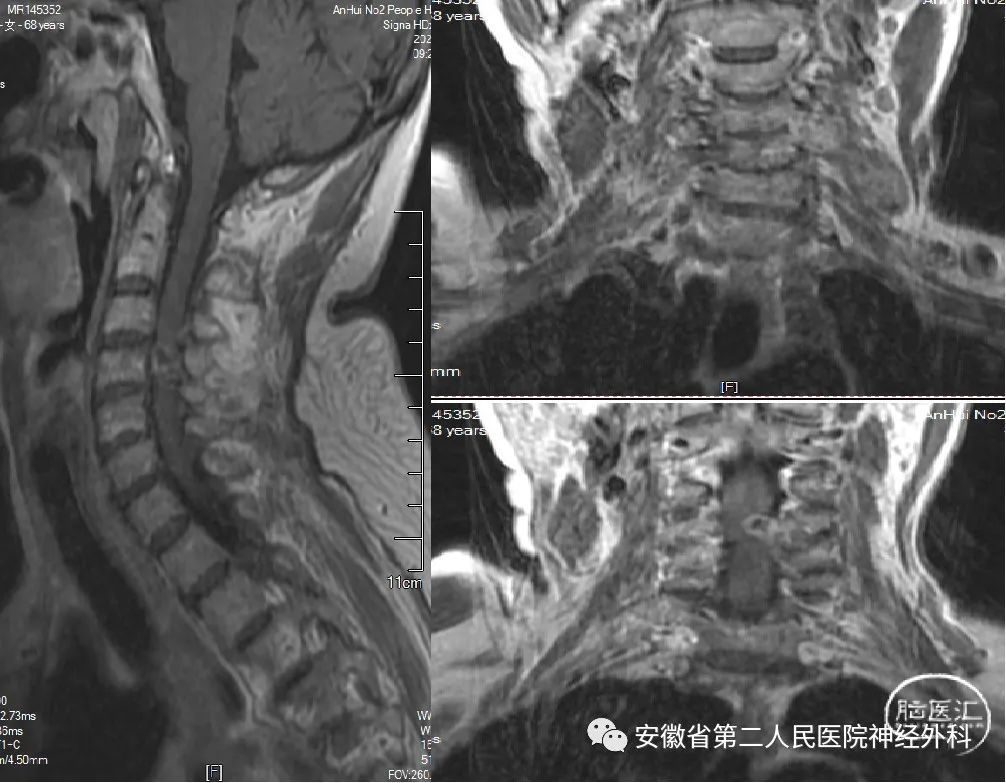

C4水平椎管内外“哑铃型”肿瘤

患者缘于2022年3月份无明显诱因下出现左侧手脚无力,走路不稳,同时伴有左侧肢体麻木感,就诊我科门诊后给予收治入科。体格检查:神志清楚,左侧肢体近端肌力约IV级,远端肢体肌力II-III级,右侧肢体肌力V-级。

术前MRI